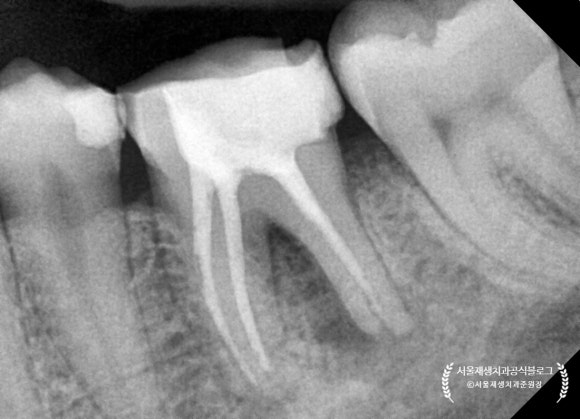

치근단 엑스레이를 살펴보겠습니다.

신경치료 후에 크라운으로 치아를 보호해주지 않고,

빈 구멍만 메워둔 상태로 몇년이 지났다고 합니다.

(프랑스에서 오신 환자분들은 대부분 크라운을 하지 않고 오시더군요. 식습관의 차이인지, 의료시스템의 차이인지...궁금합니다)

구멍을 메꾸는 재료만으로는

어금니의 씹는 힘을 충분히 견디기가 힘듭니다.

시간이 지남에 따라 재료가 마모되고 깨지면서

입 안의 세균들이 다시 치아 내부로 침투하게 되지요.

때워놓은 재료가 오래되어

하방으로 충치가 생기고 있었습니다.

신경치료 받은 치아에 충치가 다시 생긴다는 것은,

어금니 신경치료에 들인 공이 와르르 무너지는 것과 같습니다.

어금니의 신경치료 후

크라운으로 치아를 보호해주는 것은

자연 치아를 오래 쓰기 위한 필수조건입니다!